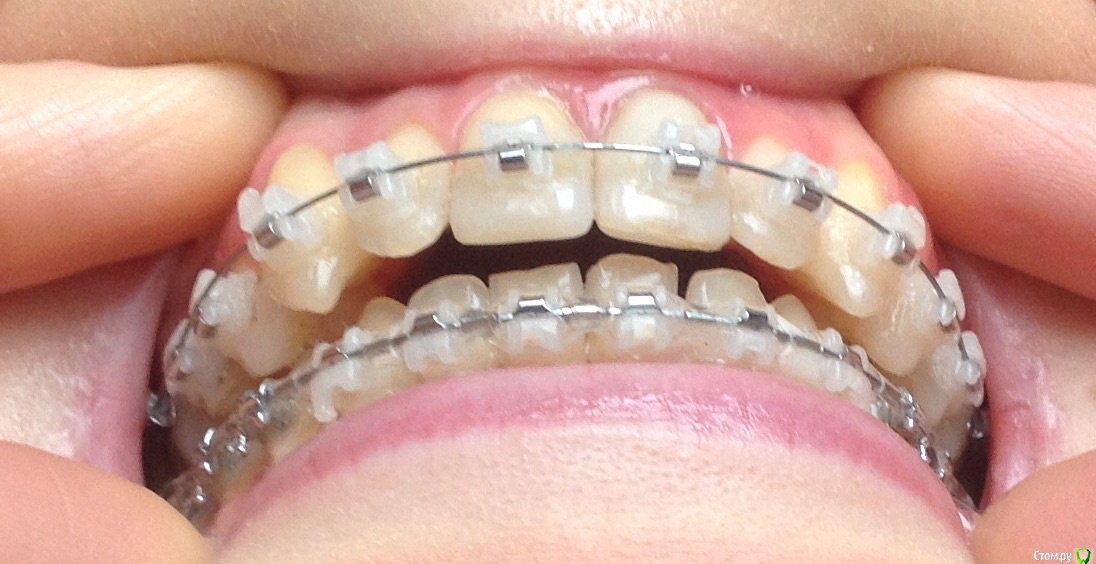

Добрый день ! Мне 29 лет. Ношу брекеты 10 мес. На данном этапе лечения сделали панорамный снимок, чтобы посмотреть ровно ли стоят корни зубов. После этого врач решил переклеить один брекет на клыке ( на снимке его видно слева ). А мне по снимку бросились в глаза , помимо этого клыка, рядом стоящий боковой резец ( он же не нравится мне как стоит и внешне) , и на нижней челюсти : 1- ый премоляр,и рядом стоящие 3 резца. Врач сказал подумать неделю и решить, хочу ли я переклеить или нет какой либо из брекетов,тк дальше они так и останутся. На её взгляд ничего переклеивать , кроме клыка, больше не нужно.

П.с. На нижн. челюсть уже поставили резинки для стягивания щелей. Я так понимаю после этого этапа уже на них брекеты не будут переклеиваться ?

Главный вопрос : Нужно ли мне переклеивать еще какие- нибудь брекеты , опускать или поднимать какой- либо из зубов, чтобы добиться большей эстетики и в дальнейшем правильного прикуса ? Или же не нужно. Заранее спасибо за внимание.